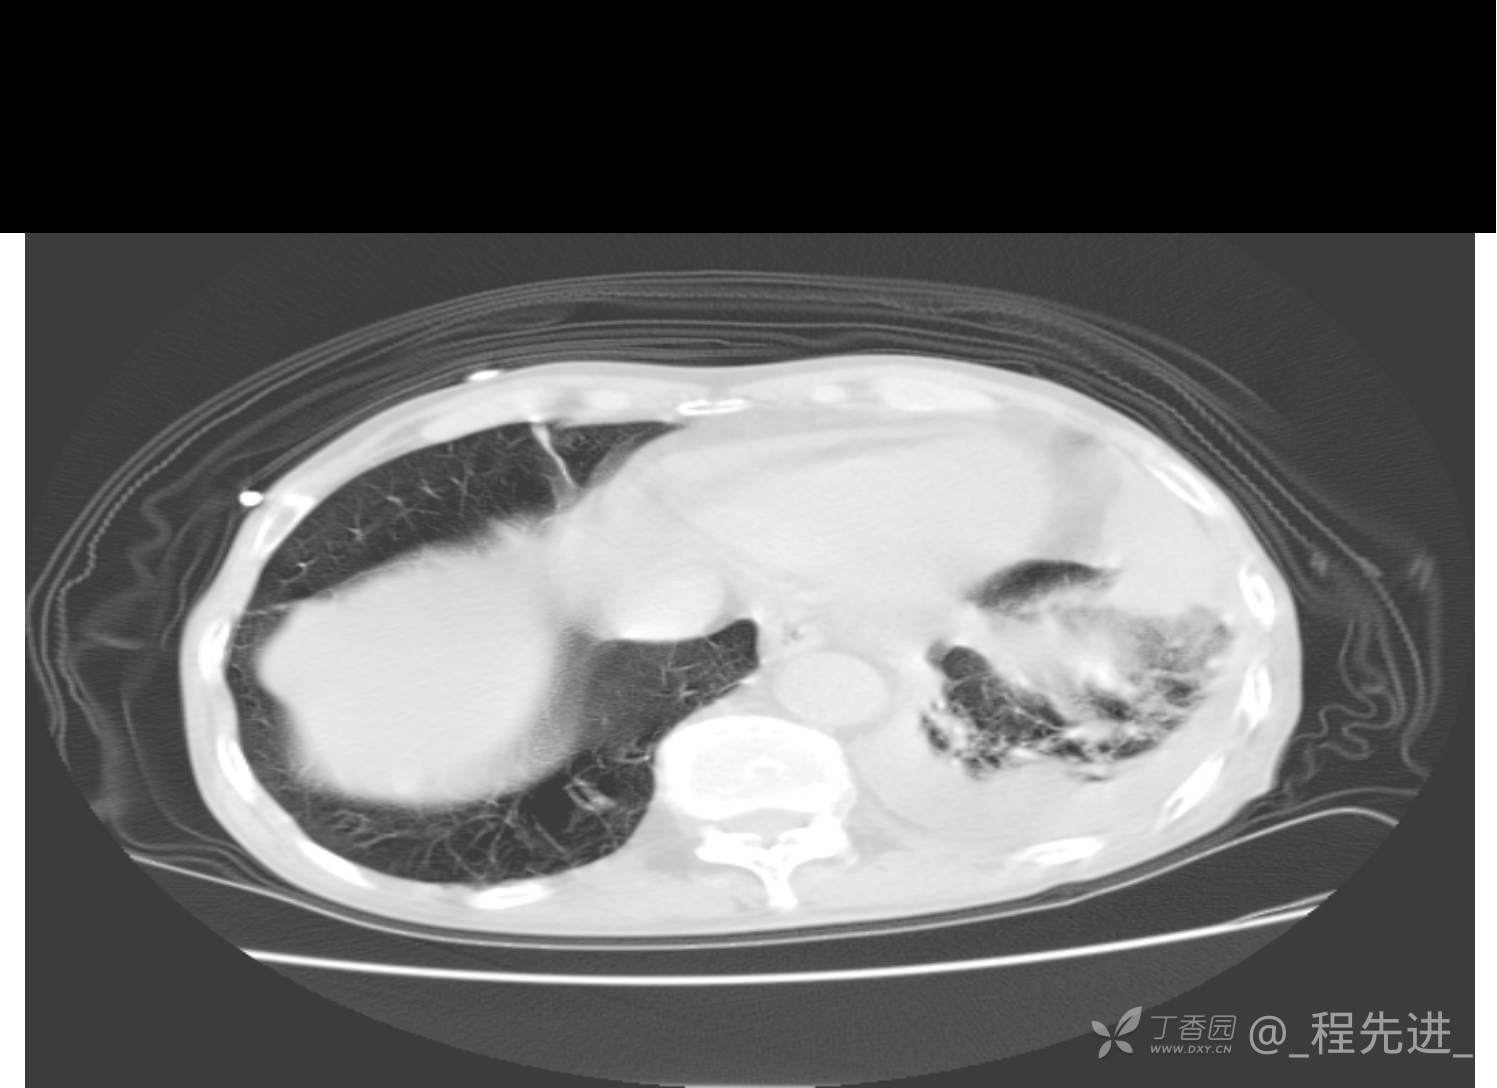

患者性别:男

患者年龄:81岁

简要病史:反复咳嗽、咳痰20余年,加重1周。两肺呼吸音低,可闻及散在干湿啰音。